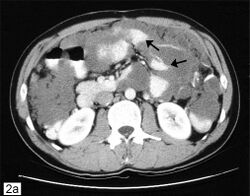

CT scanning is preferred to assess the extent of the tumor in the abdominopelvic cavity, though magnetic resonance imaging can also be used.[28] CT scanning can also be useful for finding omental caking or differentiating fluid from solid tumor in the abdomen, especially in low malignant potential tumors. However, it may not detect smaller tumors. Sometimes, a chest x-ray is used to detect metastases in the chest or pleural effusion. Another test for metastatic disease, though it is infrequently used, is a barium enema, which can show if the rectosigmoid colon is involved in the disease. Positron emission tomography, bone scans, and paracentesis are of limited use; in fact, paracentesis can cause metastases to form at the needle insertion site and may not provide useful results.[29] However, paracentesis can be used in cases where there is no pelvic mass and ascites is still present.[29] A physician suspecting ovarian cancer may also perform mammography or an endometrial biopsy (in the case of abnormal bleeding) to assess the possibility of breast malignancies and endometrial malignancy, respectively. Vaginal ultrasonography is often the first-line imaging study performed when an adnexal mass is found. Several characteristics of an adnexal mass indicate ovarian malignancy; they usually are solid, irregular, multilocular, and/or large; and they typically have papillary features, central vessels, and/or irregular internal septations.[31] However, SCST has no definitive characteristics on radiographic study.[33]

In advanced cancers, where complete removal is not an option, as much tumor as possible is removed in a procedure called debulking surgery. This surgery is not always successful, and is less likely to be successful in women with extensive metastases in the peritoneum, stage- IV disease, cancer in the transverse fissure of the liver, mesentery, or diaphragm, and large areas of ascites. Debulking surgery has usually only been done once[28] but a recent study has shown a longer overall survival in recurrent ovarian cancer when surgery combined with chemotherapy was performed compared to treatment with chemotherapy alone.[94] Computed tomography (abdominal CT) is often used to assess if primary debulking surgery is possible, but low certainty evidence also suggests fluorodeoxyglucose‐18 (FDG) PET/CT and MRI may be useful as an addition for assessing macroscopic incomplete debulking.[95] More complete debulking is associated with better outcomes: women with no macroscopic evidence of disease after debulking have a median survival of 39 months, as opposed to 17 months with less complete surgery.[26] By removing metastases, many cells that are resistant to chemotherapy are removed, and any clumps of cells that have died are also removed. This allows chemotherapy to better reach the remaining cancer cells, which are more likely to be fast-growing and therefore chemosensitive.[29]